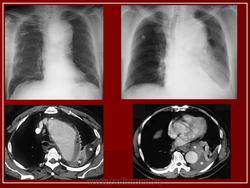

1. Аневризма грудной аорты.